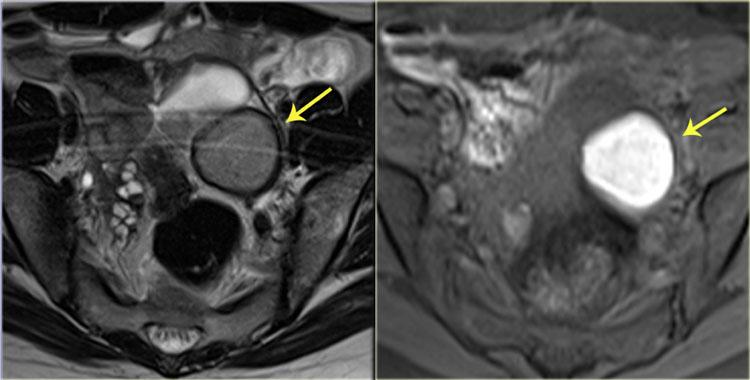

Hình ảnh T2W cho thấy hai tổn thương giảm tín hiệu hình nan quạt (mũi tên đỏ).

Những đặc điểm này điển hình cho các tổn thương lạc nội mạc tử cung xâm lấn lớp cơ thành ruột.

Ngoài ra còn có phù nề dưới niêm mạc, biểu hiện là tăng tín hiệu ở phía lòng ruột của thành ruột.

Hình ảnh T2W cho thấy hẹp khu trú trực tràng do lạc nội mạc tử cung xâm lấn toàn chu vi.